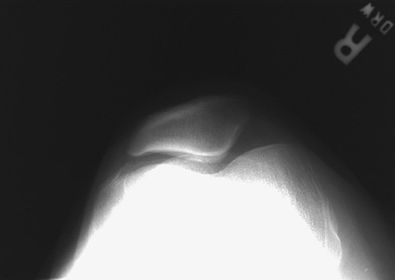

A. base of patella B. apex of patella C. tibial tuberosity D. neck of fibula E. head of fibula F. apex of head of fibula G. superimposed lateral and medial condyles H. patellar surface